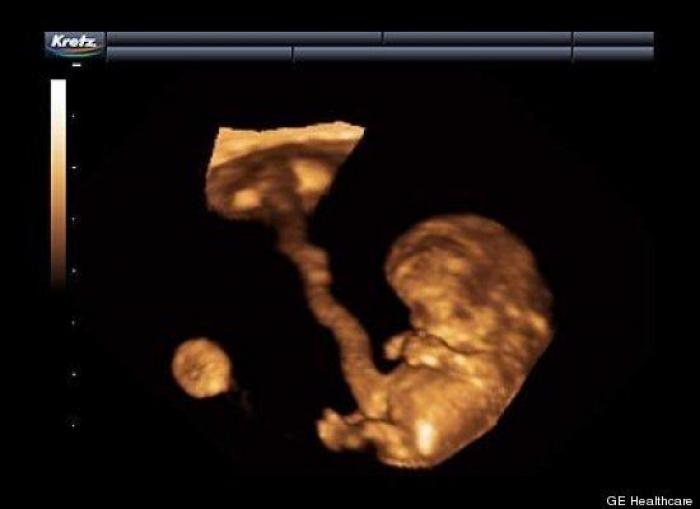

En esta galería puedes ver en fotos como es el desarrollo de un feto de semana en semana:

Desarrollo del feto, en fotos

Ver la galería